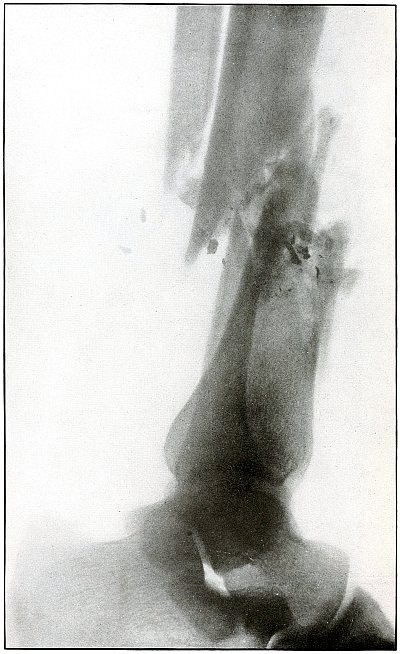

Gunshot fracture, ankle |

154 |

| 73. |

Gunshot wound, heel |

156 |

| 74. |

Gunshot wound, heel |

158 |